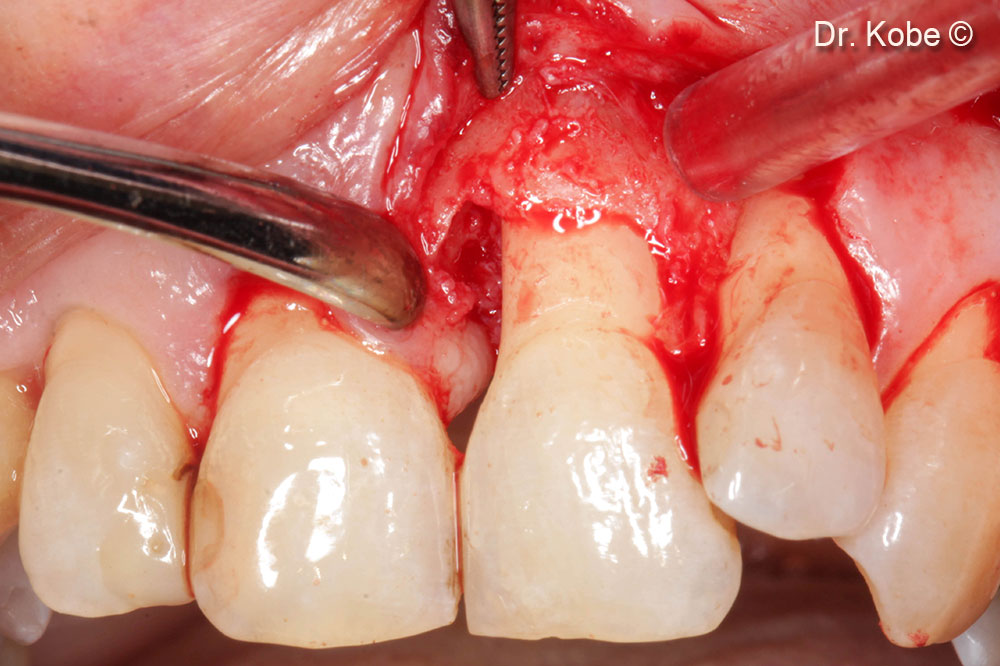

4. Access to the defect

5. Root scaling and debridement